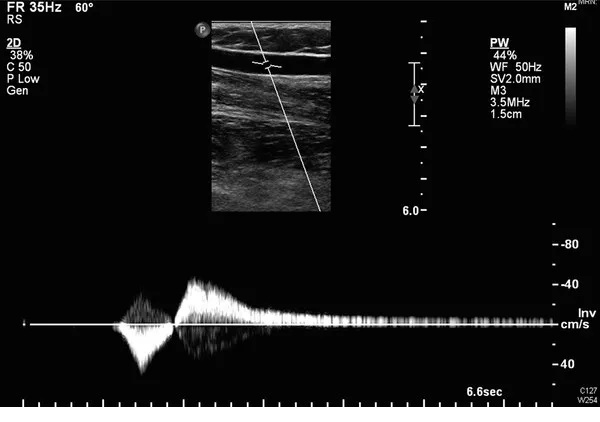

하지정맥류의 진단(혈관 도플러 초음파)

혈관초음파를 사용하여 정맥류 존재여부와 심한 정도를 확인할 수 있습니다.

정맥류의 치료는 중요한 혈관들을 다루는 것이므로 진단의 중요성은 이루 말할 수 없을 정도 입니다.

안전하고 효과적인 치료를 위해서는 심부정맥, 관통정맥, 교통정맥, 표재정맥의 기능부전과 심부정맥의 상태에 대한 상세한 정보가 필요합니다.